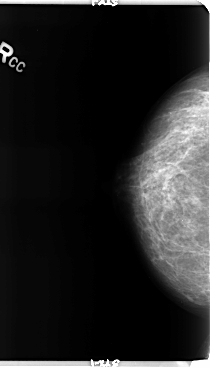

B_3150_1.RIGHT_CC

RIGHT_CC LINES 4776 PIXELS_PER_LINE 2728 BITS_PER_PIXEL 12 RESOLUTION 50 NON_OVERLAY